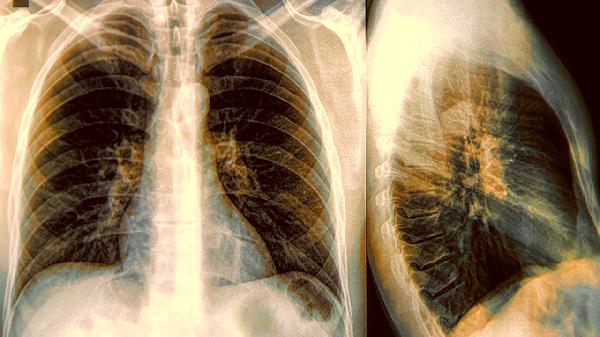

肺气囊在CT上表现为圆形或椭圆形低密度影,边界清晰。肺大疱则表现为较大的透亮区,周围肺组织受压。治疗上,肺气囊可通过影像学监测病情变化,肺大疱则需结合肺功能检查制定治疗方案。